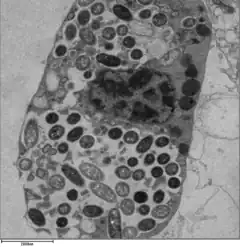

Legionella-containing vacuole

For Legionella to survive within macrophages and protozoa, it must create a specialized compartment known as the Legionella-containing vacuole (LCV).[39] Through the action of the Dot/Icm secretion system, the bacteria are able to prevent degradation by the normal endosomal trafficking pathway and instead replicate. Shortly after internalization, the bacteria specifically recruit endoplasmic reticulum-derived vesicles and mitochondria to the LCV while preventing the recruitment of endosomal markers such as Rab5a and Rab7a. Formation and maintenance of the vacuoles are crucial for pathogenesis; bacteria lacking the Dot/Icm secretion system are not pathogenic and cannot replicate within cells, while deletion of the Dot/Icm effector SdhA results in destabilization of the vacuolar membrane and no bacterial replication.[40][41]

L. pneumophila is able to invade and replicate within human alveolar macrophages. Internalization of the bacteria appears to occur through phagocytosis or coiling phagocytosis and is reliant on Dot/Icm type 4B secretion system (T4BSS). Once internalized, the Dot/Icm system begins secreting bacterial effector proteins that recruit host factors to the Legionella containing vacuole (LCV). This process prevents the LCV from fusing with the lysosomes that would otherwise degrade the bacteria. Vesicles of the host cell's rough endoplasmic reticulum are attracted to the LCV, and these vacuoles supple the LCV with necessary lipids and proteins.[13] LCV membrane integrity requires a steady supply of host lipids, such as cellular cholesterol and the cis-monounsaturated fatty acid, palmitoleic acid.[33][34] L. pneumophila replication occurs within the LCV. Once nutrients are depleted, the bacteria gain flagella and cytoxicity. To exit the host cell, L. pneumophila lyses the LCV and resides in the cytoplasm. In the cytoplasm, L. pneumophila inhibit organelle and plasma membrane function and structure which ultimately leads to osmotic lysis of the host cell.[35]